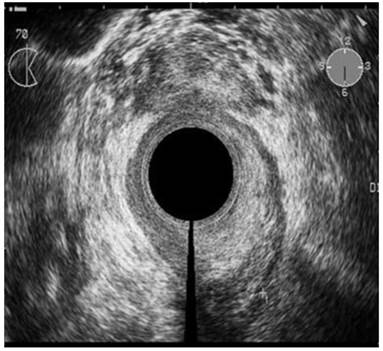

The ability of ERUS to accurately evaluate tumor response to neoadjuvant chemoradiation prior to surgical resection is hampered primarily by the effects of the chemoradiation itself: tumor necrosis, fibrosis, and peritumoral inflammation caused by therapy can significantly compromise staging accuracy. These reactions may all appear sonographically indistinguishable from residual tumor, obscuring differentiation of the five layers of the rectal wall and resulting in overstaging. In a study by Gavioli and associates, twenty-nine patients were subjected to endorectal ultrasound before and after preoperative radiotherapy. The patients then underwent a surgical resection followed by histological examination and comparison to the ERUS results.45 Morphologically and quantitatively, post-radiation endorectal ultrasound showed the reappearance of anatomic cleavage planes, a considerable shrinkage of the tumor; and in low rectal tumors, an increase in the distance from the anorectal ring in more than 50 percent of the cases. Histologic examination showed that in 28 out of 29 cases, fibrosis was the most dominant component of the irradiated lesions, varying by more than 50 to 100 percent of the lesion. A comparison of post-radiation ERUS with histopathology revealed that fibrosis became the morphologic basis of ultrasound images; therefore, after radiotherapy, what endorectal ultrasound staged was no longer the tumor, but the extent of fibrosis in the rectal wall.45 Radovanovic and associates looked at the accuracy of staging locally advanced rectal cancer after preoperative chemoradiation using ERUS. They found the accuracy of ERUS for T stage after chemoradiation was 75% in 33 of 44 patients. Overstaging occurred in 18% of patients, and 7% were understaged (Figure 6). Interestingly, five patients (11.4%) had a complete histological regression and one of these patients was staged correctly, while the other four were over staged. In the detection of perirectal lymph node metastases, ERUS was accurate in 68% of patients.46 Overall, it appears that ERUS has an important role in restaging rectal cancer after neoadjuvant treatment; however, based on the results above and other studies reporting similar results, one must take into consideration some specific changes in rectal wall and surrounding structures that can lead to false staging. Furthermore, it does not appear that it has high enough accuracy to completely differentiate a patient with a complete response from those with residual tumor.

Figure 6

Hypoechoic zone staged as T2 cancer by ERUS. Pathologic analysis of the specimen showed complete response to neoadjuvant treatment (pT0). Courtesy of Radovanovic et al. 46